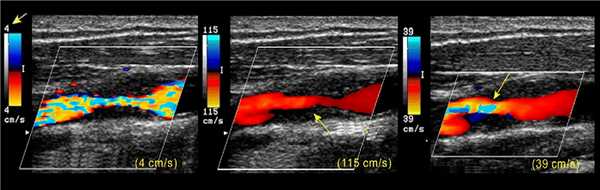

ЦДК кодирует скорость и направление в оттенки красного и синего: темные и светлые тона — низкие и высокие скорости. Когда зашкаливает cкорость, пропадает цвета чистота.

Радужные переливы (элайзинг) указывают высокоскоростной поток в месте стеноза. Настройте шкалу скорости: 4 см/с — низкая, 115 см/с — высокая, 39 см/с — правильная.